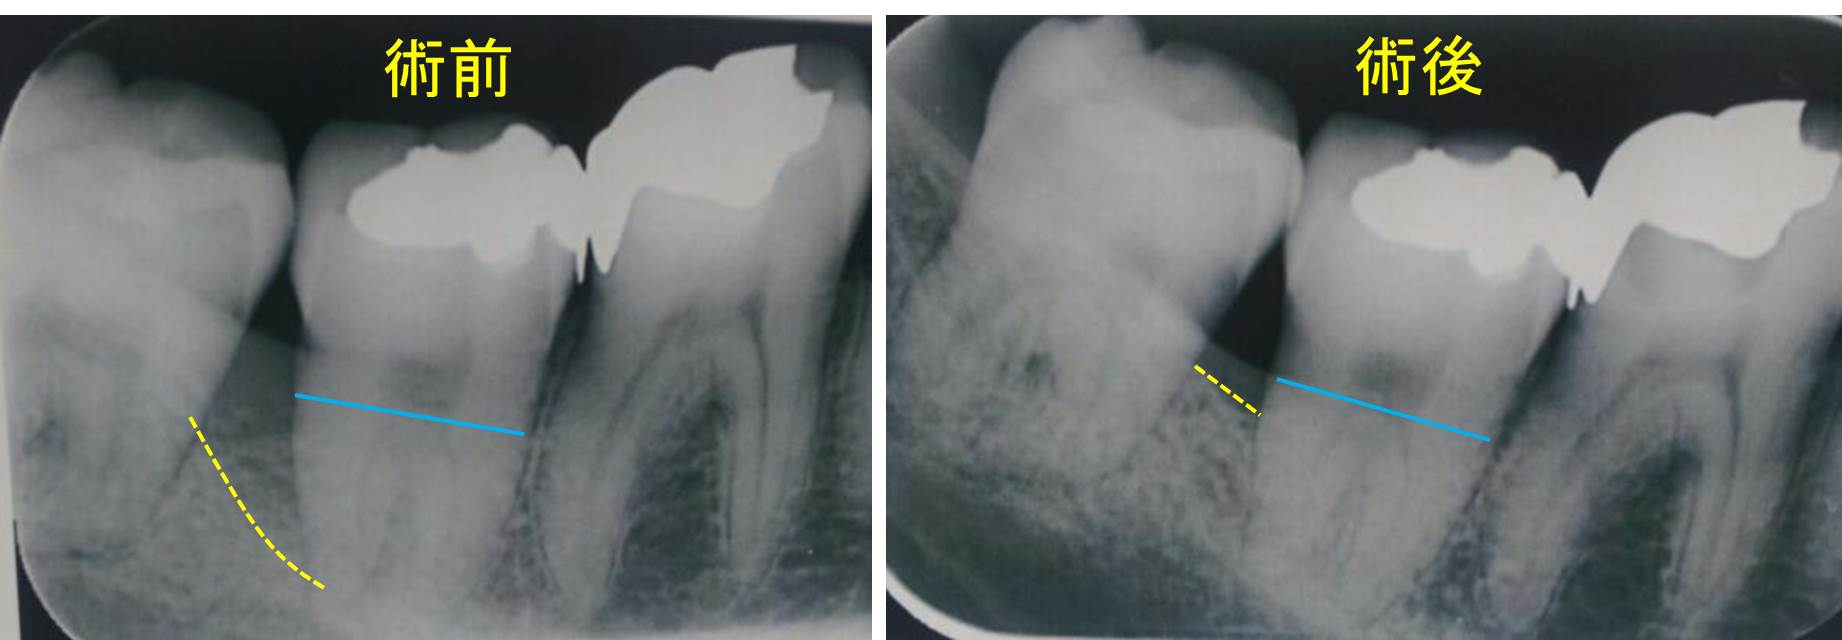

術後8ヶ月後のレントゲン写真(左が術前、右が術後)です。歯槽骨の再生が確認できます。歯周ポケットも改善し、プロービングデプスは3mmになりました。

このケースでは、プラークによる細菌感染はもちろんですが、歯ぎしりによる噛み合わせの因子が強く関わっていたため歯周炎が重篤化したと思っています。

この患者さんは、ワンタフトブラシ、歯間ブラシ、フロスと3種類の清掃器具を使ってきちんとブラッシングされています。また、夜間の歯ぎしりを防止するためにマウスピースを使用して就寝されています。

患者さんの協力があってこそ治療が成功したケースです。どれだけ上手く手術してもプラークコントロールが出来ていなければ治療は成功しません。